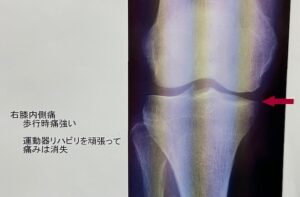

次の方 70歳 内側痛

運動療法で軽快された方ですが、

残念ながら軽快すると努力をやめてしまう。

2年後には悪化。